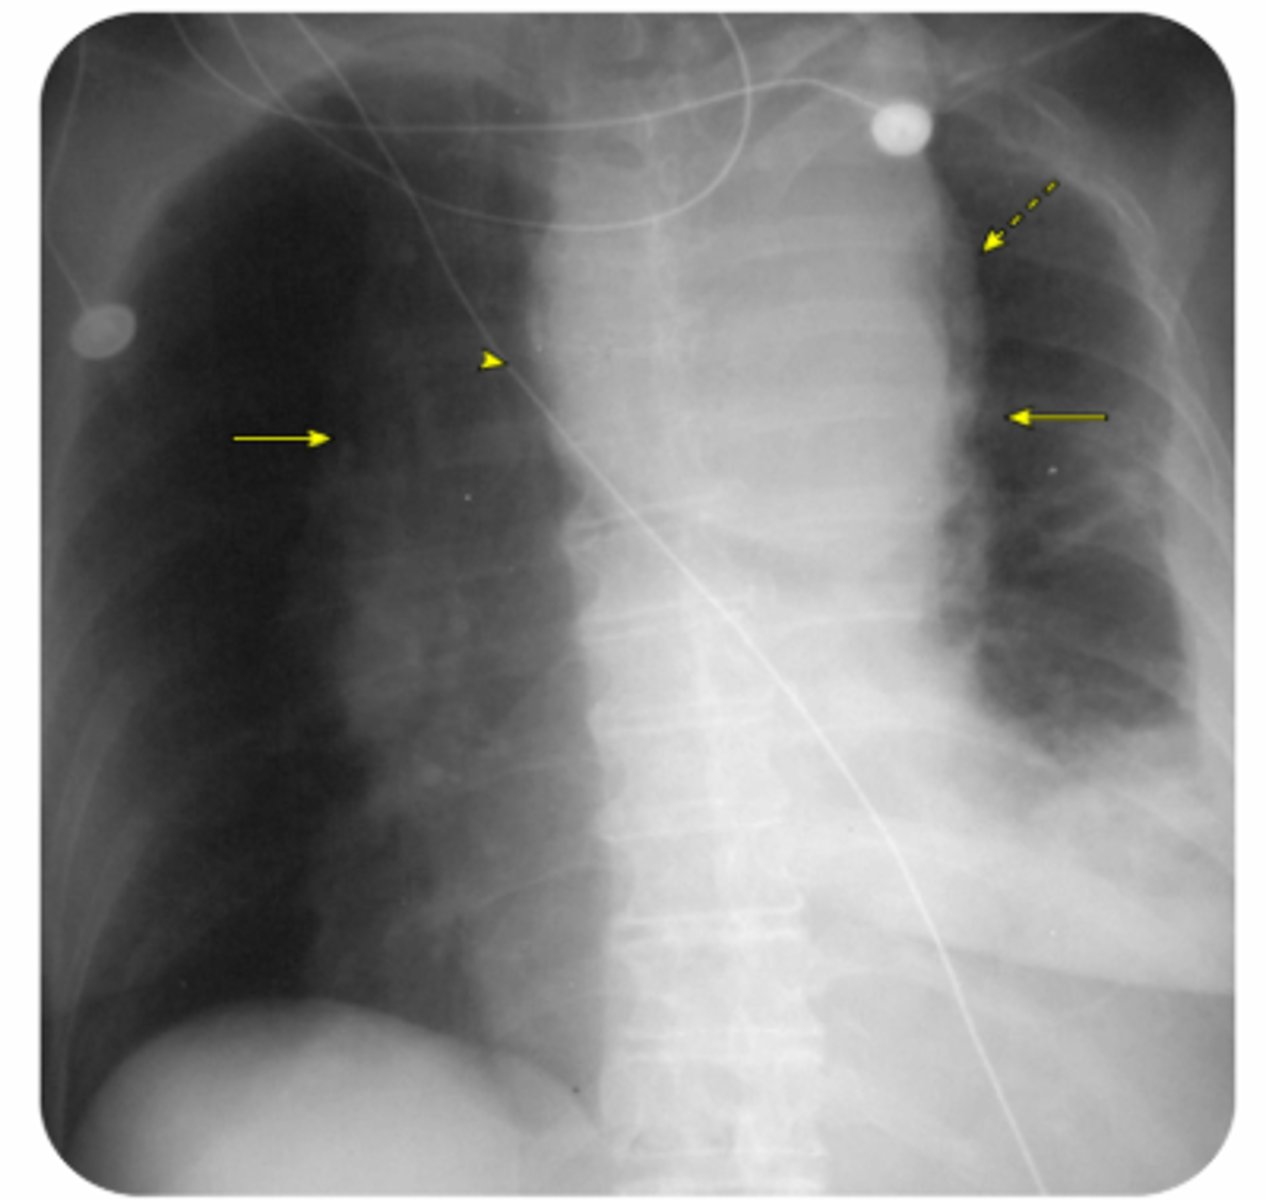

Hemothorax

Supine CXR can show opacity

Initial treatment is tube thoracostomy

Thoracotomy indications Adults: initial chest tube output > 20 mL/kg (or 1,500 mL) or subsequent output > 200 mL/hour over 3 hours

Pediatrics: initial chest tube output > 15 mL/kg or subsequent output > 2-3 mL/kg over 3 hours